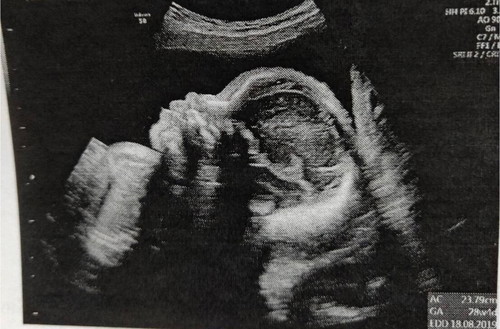

หลังจากที่เคยโพสถามไปคะ ว่ามีใครมีประสบการ์ณน้ำคร่ำเยอะบ้าง? จนตอนนี้แม่ผ่านมาหลายขั้นตอน เจาะน้ำคร่ำตรวจดาว์นก็แล้ว ผลออกมาก็ปกติ เจาะน้ำตาลแบบ 100 กรัมก็แล้วก็ปกติ จนล่วงเลยมาถึงวันนี้ ซาว์นแบบละเอียดก็ไม่พบความผิดปกติใดๆ น้ำคร่ำก็ยังเยอะเหมือนเดิม แอบงุนงง แอบสงสัย แต่ลูกปกติ อยู่ในมืออาจารย์ที่เก่งแม่ก็เบาใจไปเยอะเลยคะ วันนี้เลยเอาตัวแสบมาโชว์คะ ใครเกิดเดือนสิงหาเหมือนผมบ้างครับ ??